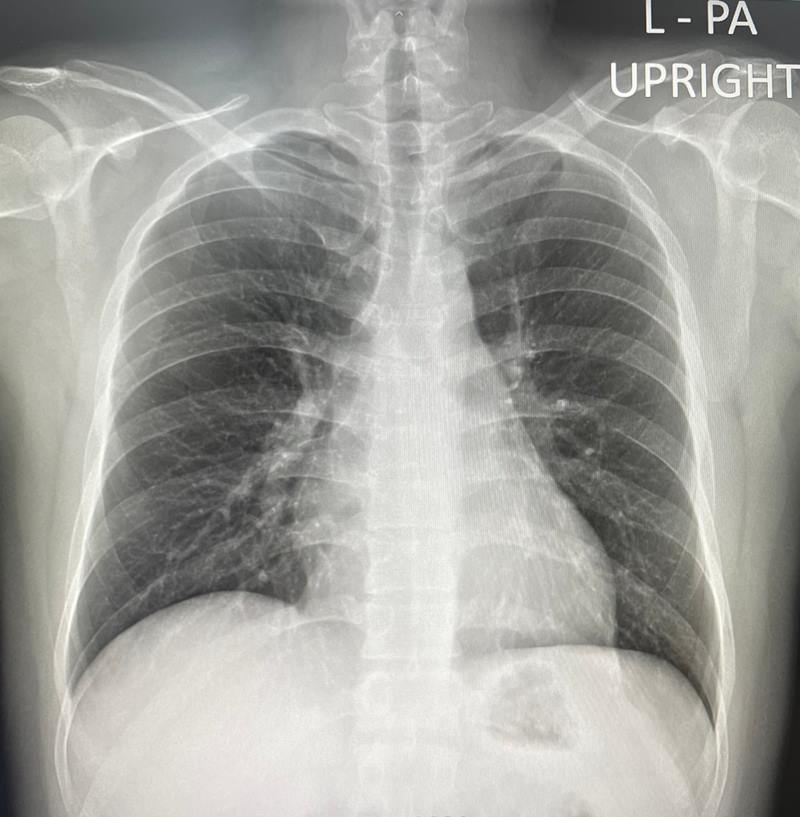

ภาพจาก เฟซบุ๊ก Nittha Oer-areemitr

สำหรับภาพที่โพสต์นั้น คือภาพฟิล์มคนไข้ที่ป่วยมา 9 วันแล้ว ไปที่ไหนก็ไม่มีใครตรวจให้จนต้องมาตรวจที่นี่ ซึ่งจากภาพเห็นว่า มีฝ้าขาวกินเนื้อปอดไปเยอะแล้ว ดังนั้นอยากให้ผู้มีอำนาจแก้ไขเรื่องนี้โดยเร็ว ตรวจให้เยอะ แยกคนไข้ให้เร็ว หาเตียงให้พอเพื่อลดระดับผู้ป่วยขั้นวิกฤตให้ได้มากที่สุด